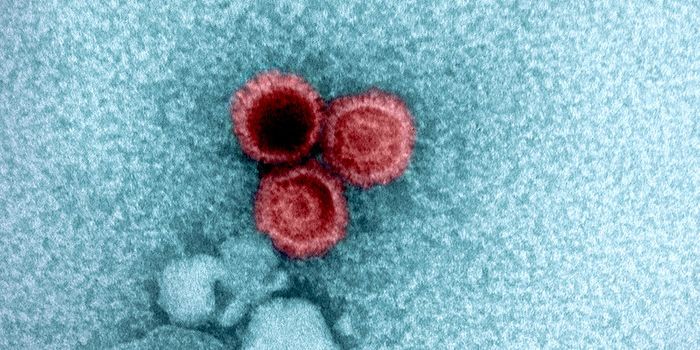

FEB 04, 2025Clinical & Molecular DXSudan virus (SUDV) can infect people to cause Sudan virus disease (SVD). Right now, an outbreak of SVD has been detected ...